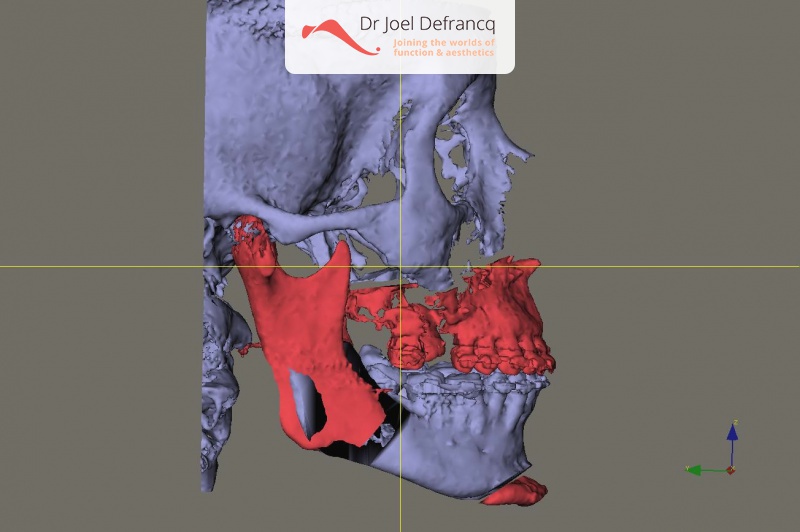

Kaakchirurgie

- Verlenging onderkaak (BSSO)

- Verlenging bovenkaak (Le Fort I)

- Vertikale verlenging bovenkaak (Le Fort I)

- Kinchirurgie

- Redo